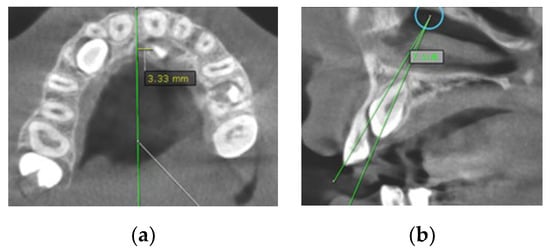

- Sagittal location (labial, palatal or median) using sagittal and coronal CBCT scans (Figure 1a);

- Horizontal position of the canine cusp tip; the canine was observed to overlap with adjacent teeth using sagittal or coronal CBCT scans. It was assigned according to Ericson and Kurol [17] (sector 1: canine overlapping by up to half the width of the lateral incisor; sector 2: canine overlapping by over half the width of the lateral incisor; sector 3: canine completely overlapping with the lateral incisor; sector 4: canine overlapping by up to half the width of the central incisor; sector 5: canine overlapping over the midline of the maxilla) (Figure 1b);

Figure 1. (a) Occlusal reference arch–location of impacted maxillary canines in axial plane; (b) horizontal position of canine cusp tip: the canine overlap with adjacent teeth in coronal plane (right maxillary impacted canine in sector 2 ad left maxillary impacted canine in sector 4).Figure 1. (a) Occlusal reference arch–location of impacted maxillary canines in axial plane; (b) horizontal position of canine cusp tip: the canine overlap with adjacent teeth in coronal plane (right maxillary impacted canine in sector 2 ad left maxillary impacted canine in sector 4).